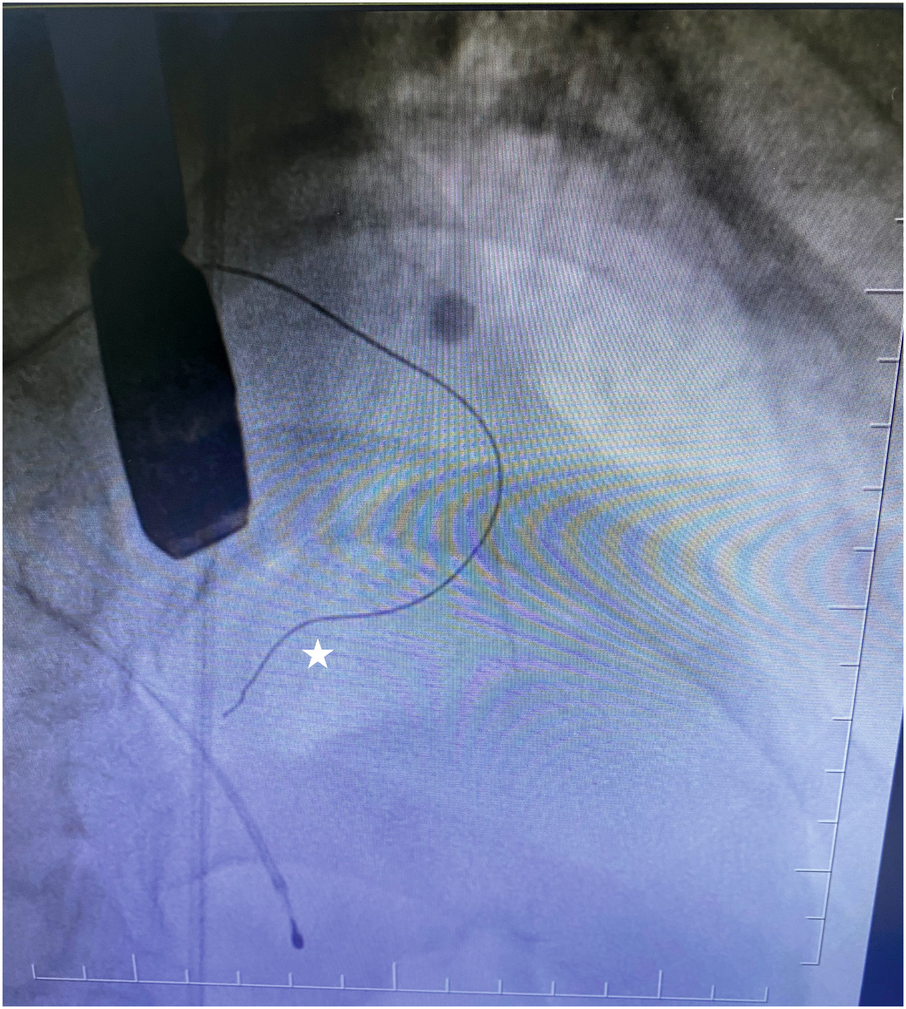

To confirm the target myocardial area in the correct perforator artery, we used our contrast agent (agitated contrast substance) via TEE. The agitated contrast substance was injected through the balloon shaft (Figure 1).

Figure 1

Coronary guidewire in the first septal branch.

To confirm the LV outflow tract obstruction–related septal artery, we reached the first septal artery by using the 0.014 guidewire. Then, the OTW balloon was advanced into the septal branch proximal segment and inflated at nominal pressure. The 0.014 wire was removed afterward. We administered 2 mL of our contrast agent (agitated contrast substance) through the OTW balloon. We observed the myocardial contrast area in the interventricular basal septum in TEE view. If it was the culprit septal artery, we injected alcohol into the target perforatory artery. If it was not, we repeated the same procedure step by step.